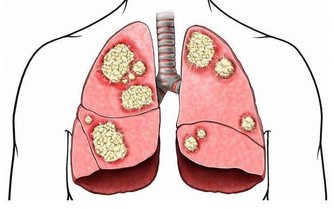

女人如果補充了足夠的維生素,患卵巢癌的機率能降低到一半,每天用3-5顆刺梨幹泡水喝,輕鬆讓卵巢恢復年輕活力。